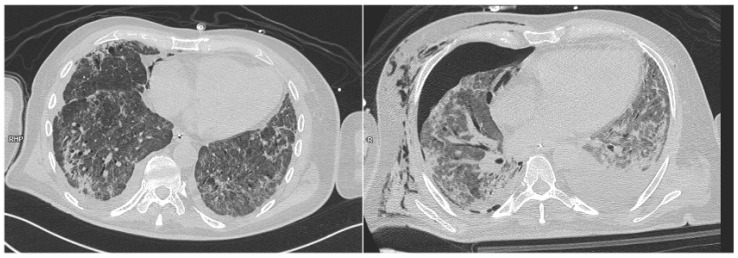

背景:麦克林效应最近在COVID-19 ARDS人群中显示出对气压创伤的高阳性预测价值。然而,关于没有SARS-CoV-2感染的ARDS人群的证据较少。我们的目的是分析COVID-19和非COVID-19 ARDS受试者,以评估Macklin效应在预测两组气压损伤发展方面的敏感性和特异性。方法:回顾性分析2018年1月至2022年11月在本中心收治的ARDS患者。经验丰富的放射科医生在胸部计算机断层扫描中检查了麦克林效应的存在。然后根据麦克林效应的存在与否将受试者分为两组,以评估其对气压创伤的预测能力。最后,我们分析了麦克林效应和气压创伤对重症监护病房和住院死亡率的影响。结果:我们分析了225例患者;在44名受试者中观察到麦克林效应。在我们的队列中,麦克林效应在预测气压损伤方面的敏感性为44.6%,特异性为90.6%。在排除COVID-19 ARDS病例后,麦克林效应的敏感性为34.7%,特异性为93.6%。尽管如此,在我们的人群中,麦克林效应的存在或气压创伤的发生并未导致ICU或住院死亡率的增加。结论:我们的分析强调,麦克林效应在预测气压创伤方面具有高特异性,但敏感性较低;此外,气压创伤的发生并不影响死亡率,这可能是由于排除了轻度至中度ARDS和纳入了大量ECMO受者。最后,麦克林效应在ARDS早期出现,可能作为肺衰弱的早期指标,可能成为转介到ARDS高级治疗中心的附加标准。

Background: The Macklin effect recently demonstrated a high positive predictive value for barotrauma in the COVID-19 ARDS population. However, there was less evidence available regarding the ARDS population without SARS-CoV-2 infection. We aim to analyze COVID-19 and non-COVID-19 ARDS subjects to assess the sensitivity and specificity of the Macklin effect in predicting the development of barotrauma in both groups. Methods: We retrospectively analyzed subjects with ARDS admitted to our center from January 2018 to November 2022. Experienced radiologists examined the presence of the Macklin effect on chest computed tomography scans. Subjects were then divided into two groups based on the presence or absence of the Macklin effect to assess its predictive power regarding barotrauma. Finally, we analyzed the impact of the Macklin effect and barotrauma on Intensive Care Unit and in-hospital mortality. Results: We analyzed 225 patients; the Macklin effect was observed in 44 subjects. In our cohort, the Macklin effect exhibited a sensitivity of 44.6% and a specificity of 90.6% in predicting barotrauma. After excluding the COVID-19 ARDS cases, the Macklin effect showed a sensitivity of 34.7% and a specificity of 93.6%. Nonetheless, in our population, the presence of the Macklin effect or the occurrence of barotrauma did not lead to increased ICU or in-hospital mortality. Conclusions: Our analysis highlighted that the Macklin effect demonstrates high specificity in predicting barotrauma but a low sensitivity; moreover, the development of barotrauma did not impact mortality, possibly due to the exclusion of mild to moderate ARDS and the inclusion of a significant number of ECMO recipients. Finally, the Macklin effect appears early during ARDS and may serve as an early indicator of lung frailty, potentially becoming an additional criterion for referral to centers for advanced ARDS treatment.